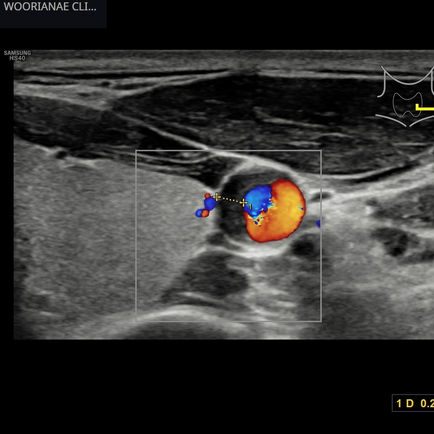

초음파 영상의학 센터

(12)

게시물 12개